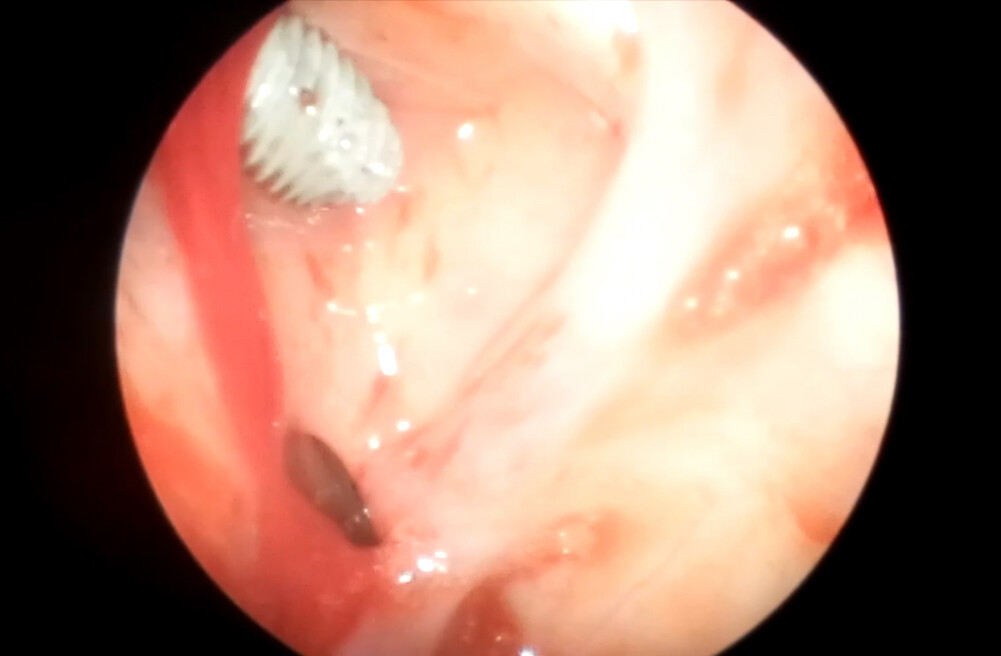

Осложнение операции открытого синус-лифта в амбулаторной практике стоматолога хирурга-имплантолога в виде верхнечелюстного синусита хоть и встречаются редко, но всегда запоминаются и выбивают врача из колеи повседневной работы.

Докладчик предложит алгоритмы принятия решения в случае получения осложнения.